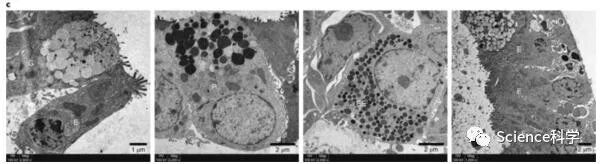

使用透射电子显微镜,研究者在分化的蝙蝠肠样中鉴定出具有四种主要肠道细胞类型特征的细胞,包括肠上皮细胞(E),杯状细胞(G),潘式细胞(P)和肠内分泌细胞(EE),如下图所示:

尽管有一条蝙蝠小肠类器官连续扩增了12周,但其他四条蝙蝠小肠类器官在4或5周后就停止了活性增殖,可作参照的是,人的肠类器官可以连续扩展至少1年。尽管如此,研究者还是建立了第一个模拟蝙蝠肠上皮细胞组成的蝙蝠肠类器官。